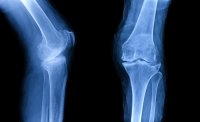

Kireçlenme tanısı tıbbi öykü, ayakta çekilen diz röntgenleri ile konulur. Başlangıç dönemlerindeki kireçlenmelerde EMAR tetkiki yararlıdır. Şunu asla unutmamak gerekir; hastaların şikayetleri ile görüntüleme bulguları her zaman uyuşmayabilir. Hiçbir şikayeti olmayan hastaların röntgen ve EMAR’larının kötü olabildiğini ya da çok şiddetli ağrıları olan hastaların tetkiklerinin daha normal olabildiğini çok sık görüyoruz. Hal böyle olunca kireçlenme tedavisi görüntüleme bulgularına göre değil, hastanın şikayetlerine göre planlanmalıdır. Diz kireçlenmesinde tedavi yaklaşımı şöyledir.